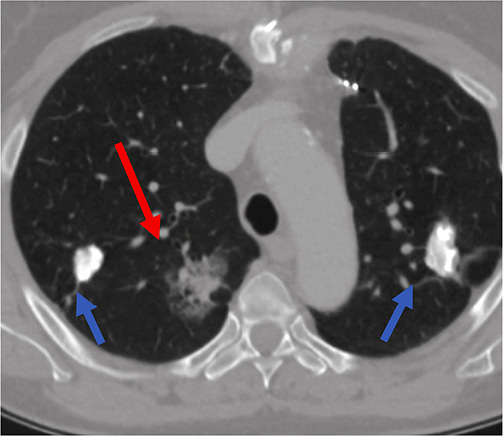

Figure 3. Head CT performed immediately after lung biopsy depicted air (white arrow) in cortical arteries in the left parietal lobe – finding representing air embolism due to lung biopsy.

Immediate head CT was performed suspecting neurological pathology. Small air foci were found in peri­pheral area of left parietal lobe – a clear sign of air embolism (Figure 3). Patient was treated with 100% oxygen.